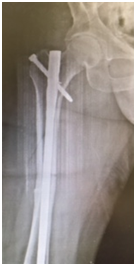

We report a case of bilateral femoral fracture in a patient after 7 years of treatment with alendronate at a dose of 70 mg weekly. The patient was a 67 y.o. female with no history of any comorbidity such as diabetes, alcohol abuse, smoking, chronic use of glucocorticoids or others. She fell from her own height in March 2014, resulting in a transverse femoral shaft fracture of the left femur (Figure 1A), treated with a blocked anterograde intramedullary nail (Figure 1B & 1C). In June 2016, she suffered a contralateral short oblique femoral fracture with no history of direct trauma, presumably with a torsional mechanism - rotation around the body axis (Figure 2A). The treatment of choice was also a blocked anterograde intramedullary nail (Figures 2B & 2C). We can observe in Figures 1 & 2 the absence of compromised trabecular bone or thinning of cortical bone, corroborating the probable pathophysiology behind bisphosphonate-associated fractures - decreased bone remodelling - and not osteopenia/osteoporosis.

Figure 1A Left femoral anteroposterior radiograph - Simple short oblique tract fracture with cortical thickening. 1B & 1C Postoperative radiograph – anterograde blocked nail left femur.